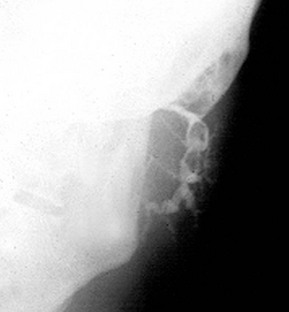

Plain X-rays demonstrate most calculi. For the submandibular gland and duct, an occlusal film held between the teeth shows the floor of the mouth, and a lateral oblique gives a second viewpoint. For the parotid, AP and lateral views are often used. Contrast radiography of the ducts (sialography) is sometimes indicated if the history suggests stone disease yet no stone is palpable or visible on plain X-ray, although this has largely been replaced by ultrasound. Sialography (Fig. 47.7) requires cannulation of the salivary duct which may reveal a stenosis of the orifice and may relieve symptoms temporarily. Stenosis alone of any part of the duct may produce symptoms similar to calculus obstruction.

This uncommon condition may occur at any age and usually affects the parotid. One or both glands are subject to recurrent attacks of painful swelling. The cause is low-grade bacterial infection usually without duct obstruction. Recurrent attacks cause chronic swelling. Sialography shows dilatation of the duct system with terminal sacculation described as sialectasis. The cause is often a duct orificial stenosis, or stenoses of unknown origin proximally in the duct.